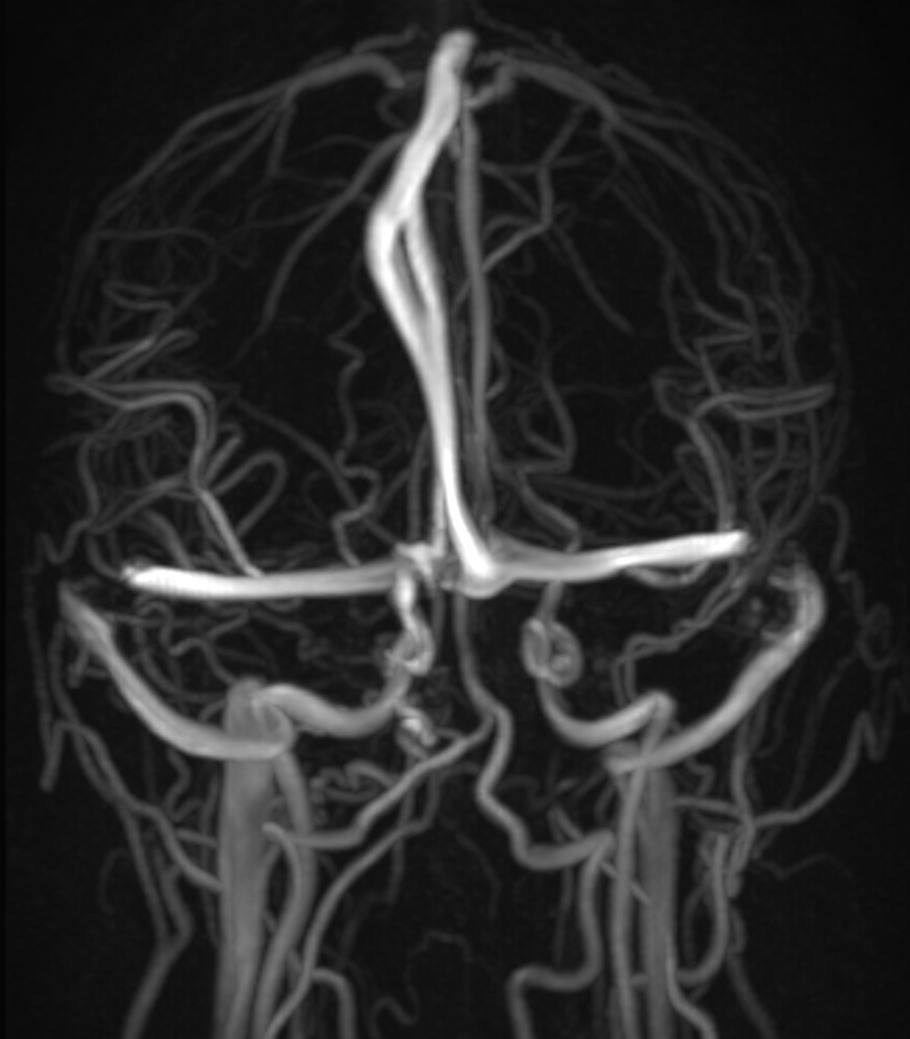

Image IQ Quiz: 30-Year-Old Woman Presents with Papilledema

A 30-year-old female presents with papilledema. What is the imaging finding?

What is your diagnosis?